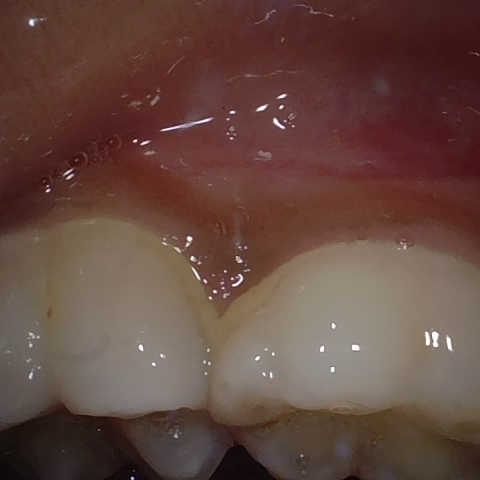

Annotated as "Good"